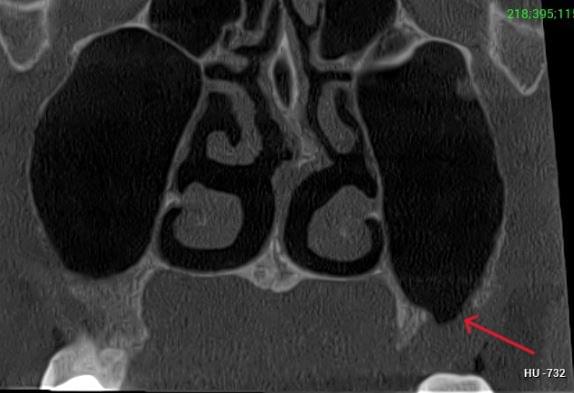

КПКТ (конусно-променева комп’ютерна томографія) — це 3D-знімок високої роздільної здатності. На відміну від звичайного рентгену, КТ показує:

Важливо: Якщо нежить триває понад 2 тижні, з’явилася температура, набряк обличчя чи біль в очах — не відкладайте візит до ЛОРа. Раннє КТ пазух носа дозволяє виявити приховані кісти, поліпи, сторонні тіла або одонтогенний гайморит ще до ускладнень.